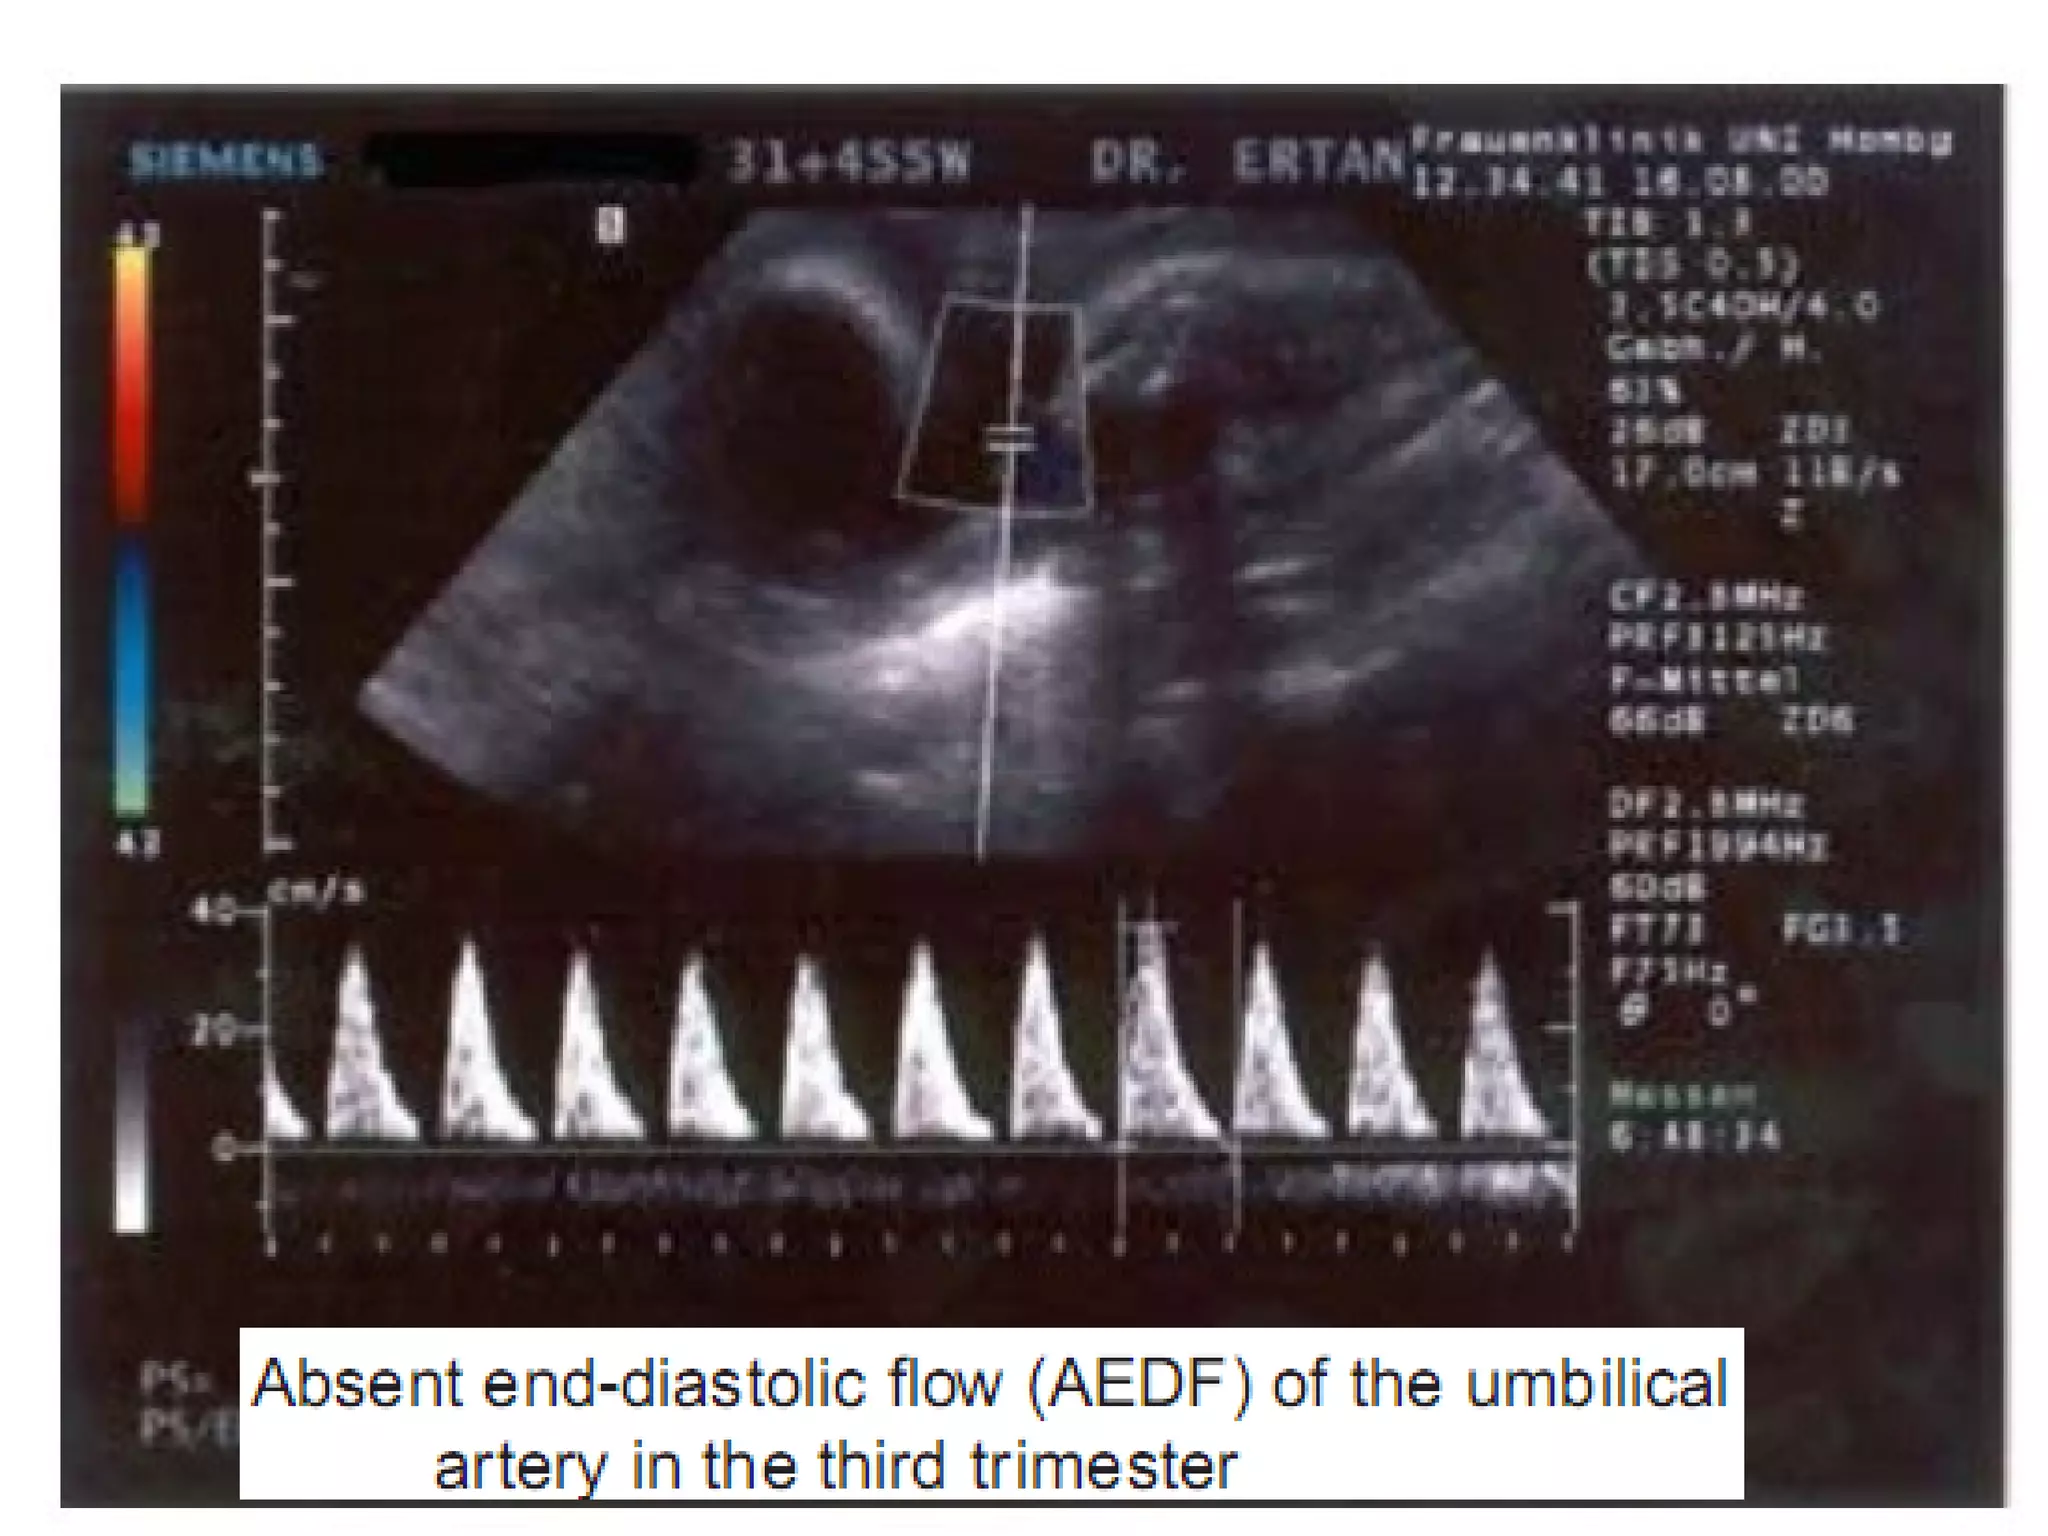

Umblical Artery doppler- In IUGR there is

increased umblical artery resistance (increased

S/D ratio), absent end diastolic flow and finally

reversed end diastolic flow.

Perinatal mortality rate increases significantly in

fetuses with absent end diastolic flow (9-41%)

and reversed end diastolic flow (33-73%) in

umblical artery.